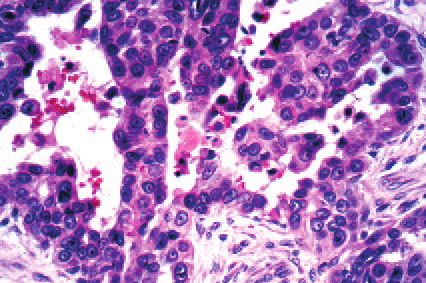

Read MoreAdenoid (acantholytic) scc = الكارسينوم شائك الخلايا الغداني منحل الاشواك

Read MoreAdenoid cystic carcinoma=كارسينوما كيسية غدانية OLYMPUS DIGITAL CAMERA